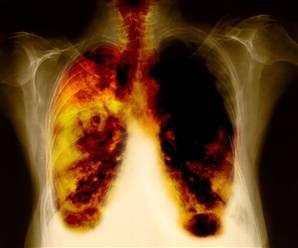

فقدان الشهية وتورم الوجه.. تعرف على أعراض سرطان الرئة

يعتبر سرطان الرئة من أشد أنواع السرطانات خطورة، حيث يعاني منه الكثير من الناس حول العالم، وهناك بعض الأعراض التي تشير إلى احتمالية الإصابة بسرطان الرئة، وإليك أهم تلك الأعراض.

أعراض سرطان الرئة:-

هناك بعض الأعراض التي في حالة ظهورها، يجب اللجوء إلى الطبيب على الفور، قبل أن تزيد الخطورة، حسب ما جاء في صحيفة "إكسبريس".

سعال الدم.

الإصابة بالتهابات الصدر.

سعال طويل، ربما يستمر لأسبوعين أو أكثر.

الشعور بألم عند التنفس.

ضيق التنفس.

الشعور بالتعب المستمر.

صعوبة البلع.

صفير.

الشعور بالإرهاق الشديد.

ظهور تغيرات في شكل الأصابع.

أعراض سرطان الرئة الأقل شيوعا

هناك بعض الأعراض الخاصة بسرطان الرئة ولكنها ليس شائعة مثل الأعراض الأخرى، وإليك أبرز تلك الأعراض، نادرة الحدوث، ولكن يجب عدم الاستهانة بها، لأنها ربما تكون مؤشرا قويا على سرطان الرئة.

تغير في نبرة الصوت، ليكون مثل الصوت الأجش.

ظهور تورم في منطقة الوجه والرقبة.

ألم مستمر في منطقة الصدر.

آلام في الكتفين.

عدم القدرة على بلع الطعام بالشكل الطبيعي.

قد تصبح الأصابع أكثر انحناءا من قبل.